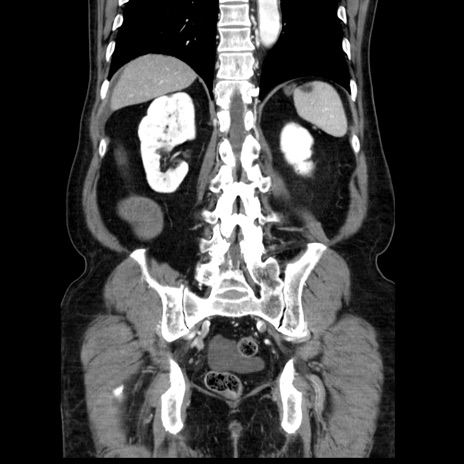

症例30(冠状断像)

【症例】80歳代男性

【主訴】臍周囲痛

【現病歴】約6時間前から臍下部痛が出現。次第に腹部膨隆・背部痛も生じてきたため来院。背部痛の場所は変化しない。

【既往歴】腎盂腎炎

【身体所見】意識清明、BT 36.3℃、BP  131/87mmHg、P 87bpm、SpO2 100%(RA)、臍周囲自発痛・圧痛あり、反跳痛なし、自発痛部位に一致して板状硬あり、腹部膨隆、腸雑音減弱、CVA tenderness両側陰性。

【データ】WBC 19600、CRP 0.33